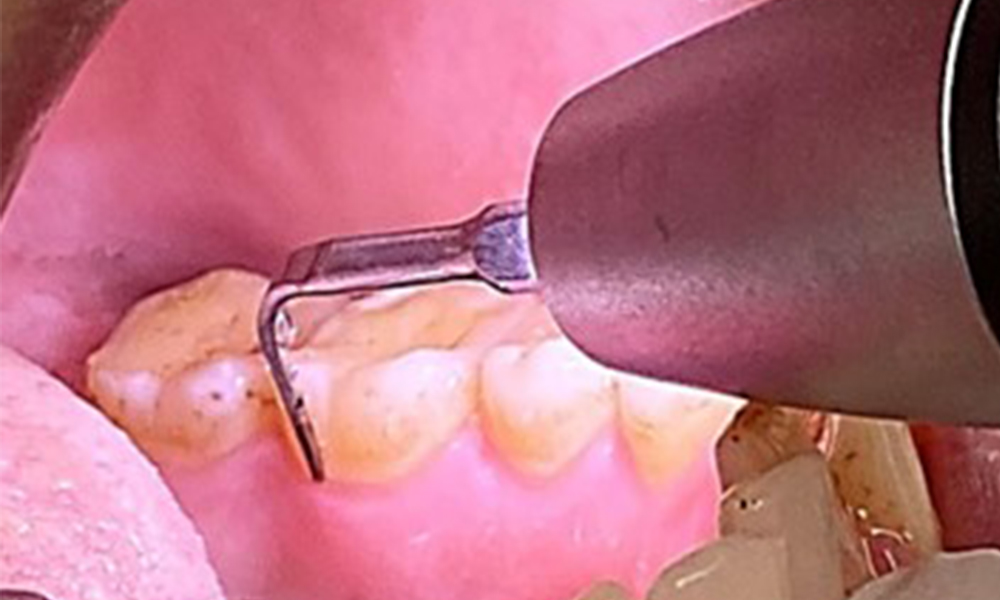

Ziel ist es durch supra- und subgingivale Biofilmentfernung das Erkrankungsrisiko zu kontrollieren. Die Wahl der Instrumente erfolgt

bedarfsgerecht. Zunächst sind Zahnstein und ggf. Konkremente mit Ultraschall und / oder Handinstrumenten zu entfernen (Abb. 10).